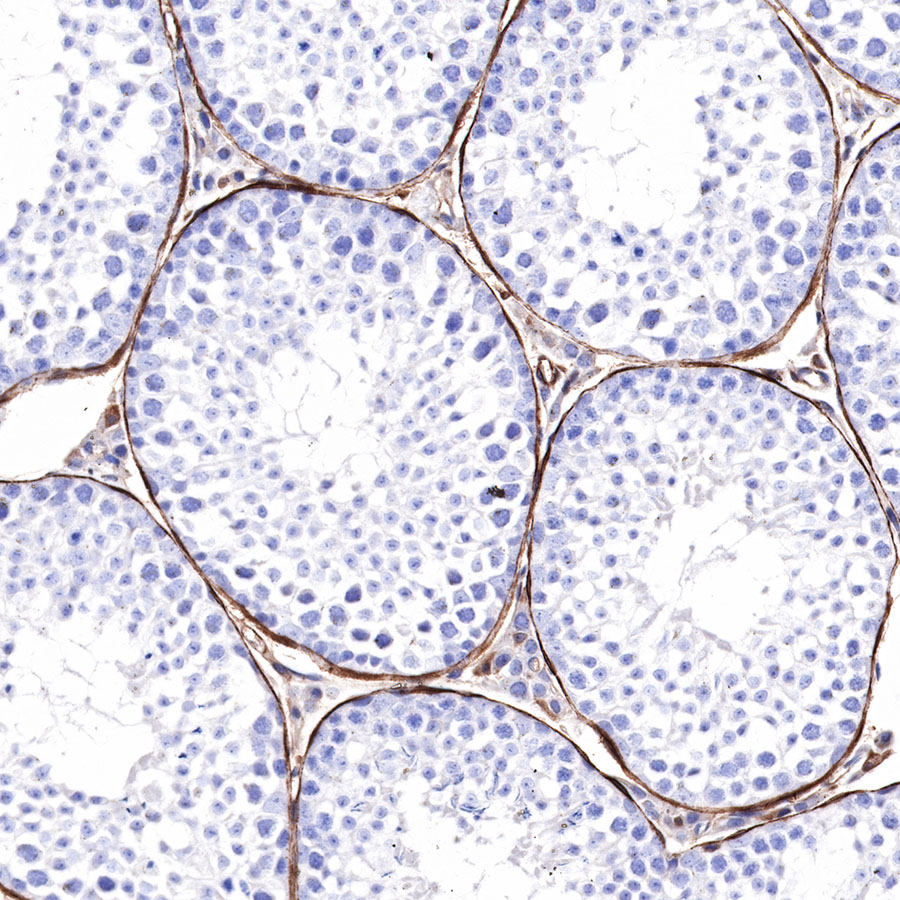

Immunohistochemistry